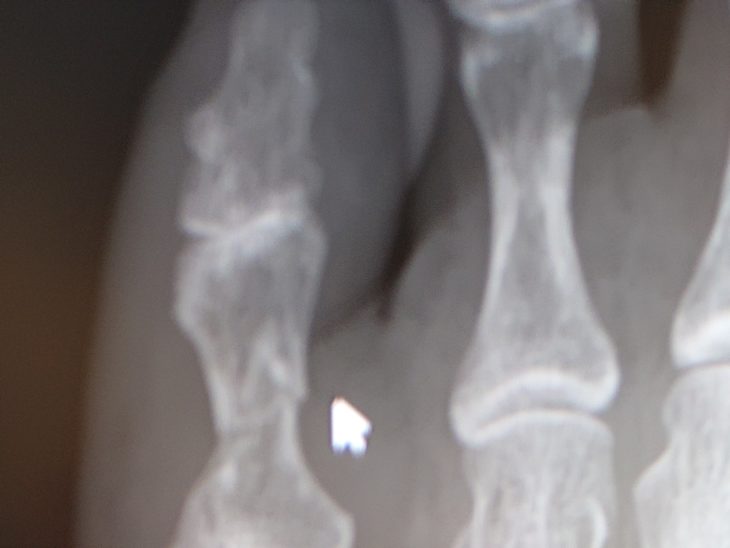

診察して レントゲンを撮ったら

周りの皆んなは 「打撲だと思うよ」って 言うけど、、この痛みと腫れは脱臼か骨折かもと 思っていたら ヤッパリ 骨折だった。

しばらく経過観察ですと言われて、、、カカトで歩くように、、土踏まずに型を取った石膏のようなものを入れて、、小指を安静にするようにと、、。